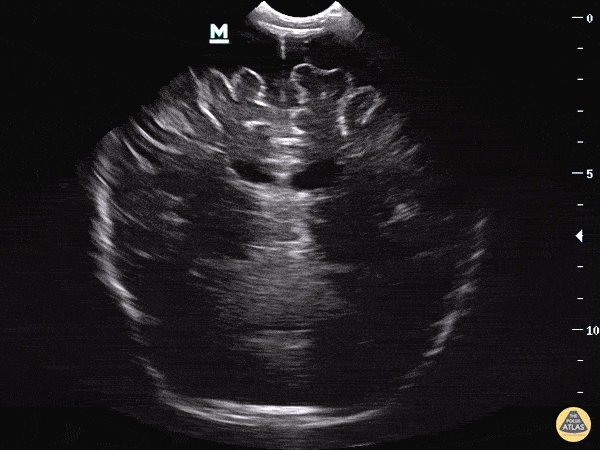

Clip 1: You notice significant enlargement of the extra axial space seen most clearly in the 12 o’clock position above the interhemispheric fissure.